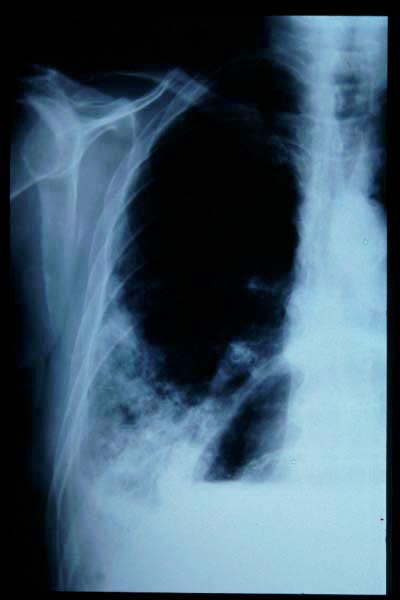

Fractura impactada de húmero .

Fractura de húmero, intensa desviación de fragmentos

Fractura de húmero.

Fractura compleja de húmero.